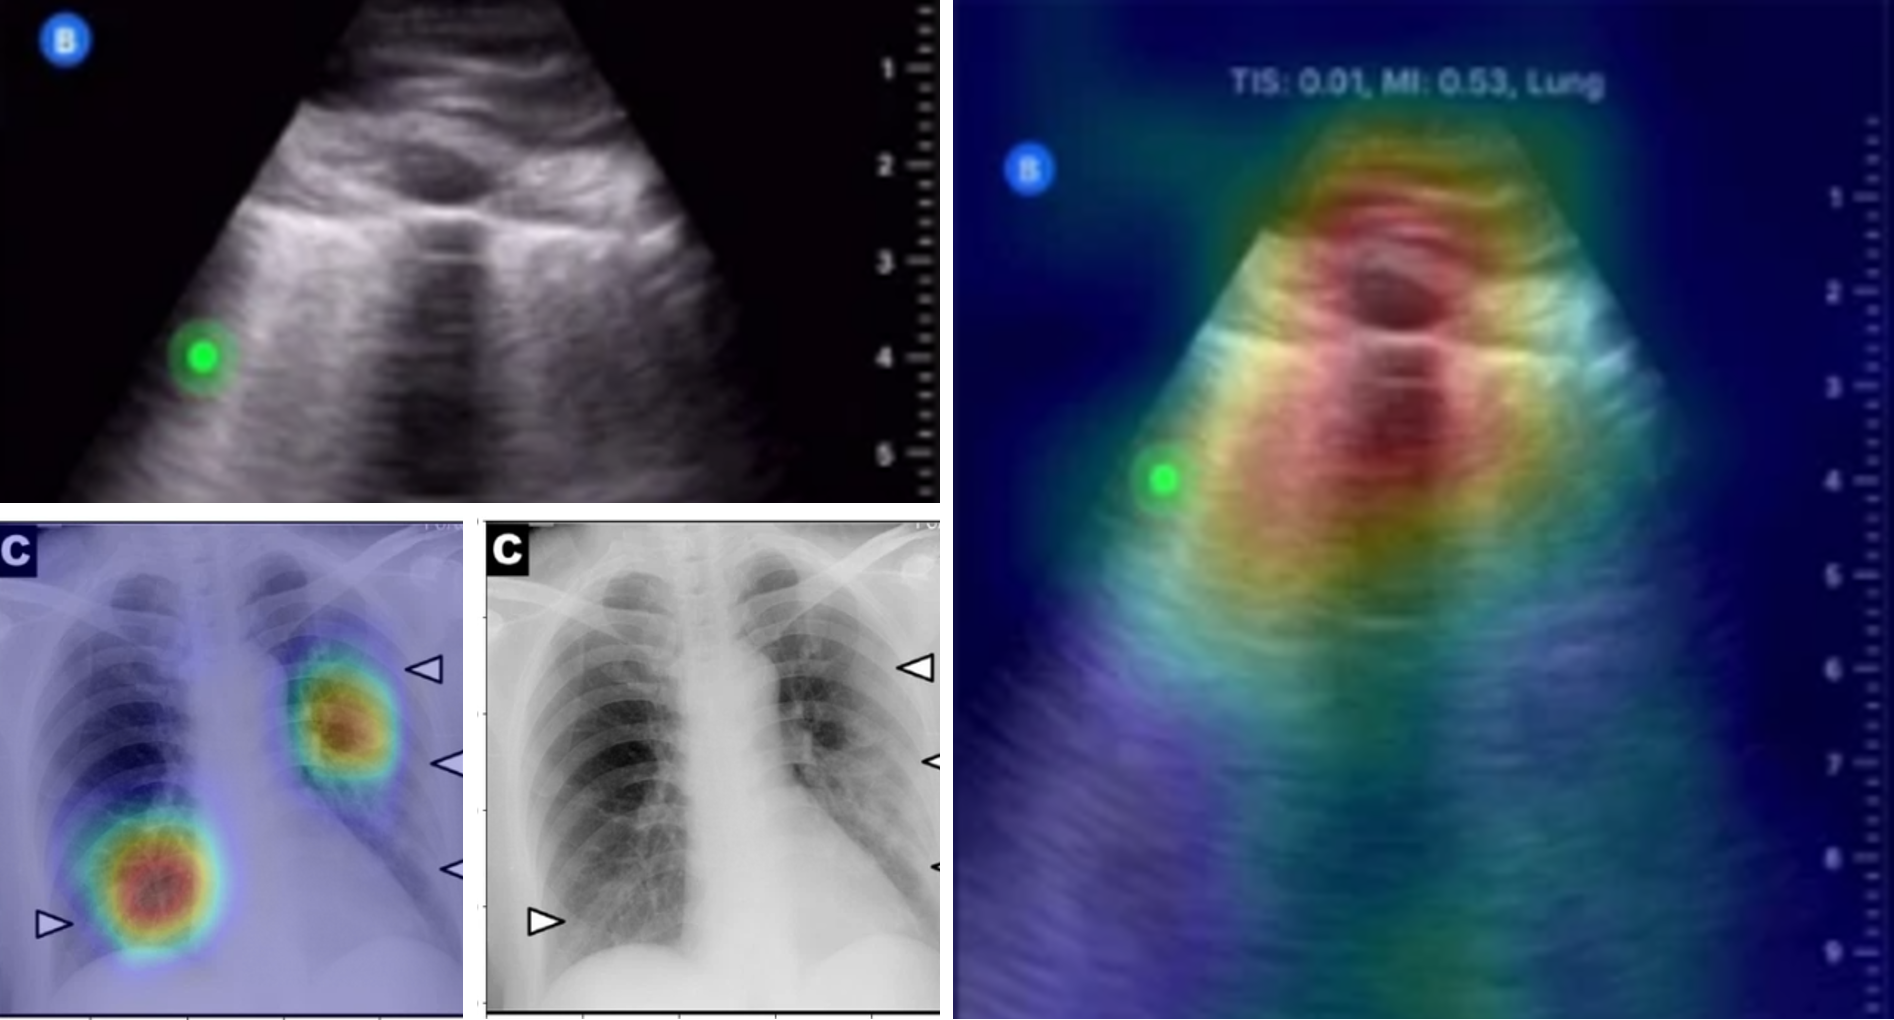

With this first batch of images and others coming from Chinese studies, the team developed two algorithms. One gives the probability of infection and the other, a heat map of the affected areas. Near the end of March, they put up a website that allows medical professionals to upload and obtain readouts for their X-ray images.

“When the Institut du Savoir Montfort joined us, the project took a whole other dimension,” adds Akhloufi. The Hôpital d’Ottawa’s research institute supplied them with more images to improve the tool. Akhloufi says that predictions on a set of more than 5,000 images are now close to 98 per cent accurate and will only get better with more data.